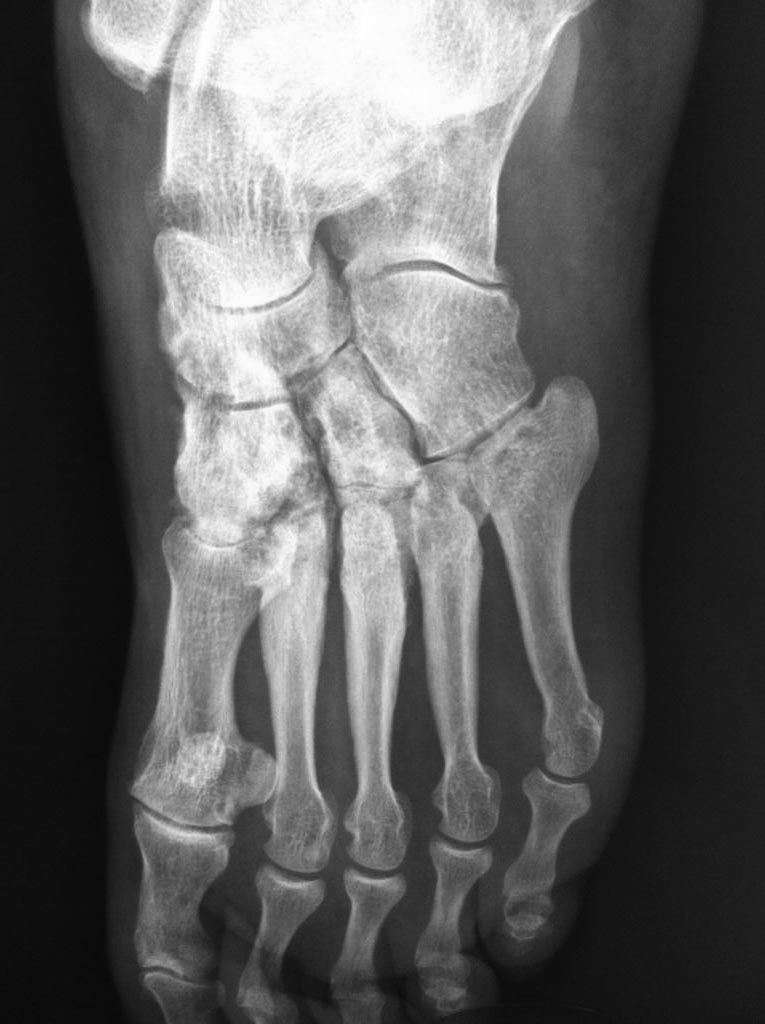

Асептический некроз костей среднего отдела стоп.

Доброго времени суток. Обратился пациент, 62 года, бытовые и трудовые условия в данное время не отягощены и не были никогда тяжелыми, без вредных привычек,

со слов оперативных вмешательств не было, курсов гормональной терапии не получал, периодически принимает лекарственные препараты от арт. гипертензии. Без видимых причин около 1 года назад появились боли в стопах при ходьбе и нагрузке, в связи с чем обратился к ортопеду.

Лаб исследования: Ревмофактор, С-реакт. белок, АЦЦП, Мочевая кислота и др. в пределах возрастной нормы. Хотелось бы услышать мнения. Заранее благодарен.

Добрый день. Похоже на Charcot

И, забыл добавить, есть мнение, что ингибиторы АПФ, например эналаприл, эту саму артропатию Шарко могут вызывать.